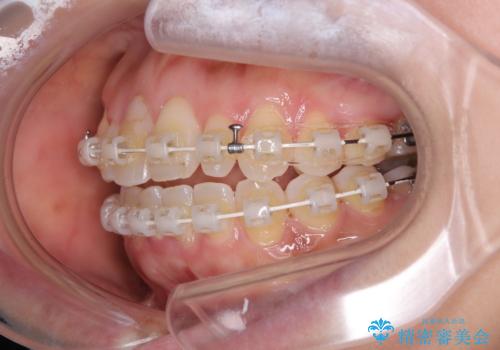

- 審美装置

- 2年1ヶ月

下顎骨が左側にズレて成長してしまったため、左側の咬み合わせが上下反対になっている状態でした。

そこまでの処置は望んでいらっしゃらなかったため、歯列矯正でのカムフラージュにより咬み合わせを改善することとしました。

予想通り左側の咬み合わせの調整に苦労をしましたが、最終的には違和感のない咬み合わせを達成することができました。